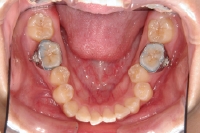

下顎の奥歯にバンドを装着

下顎の外側にセラミックブラケットを装着